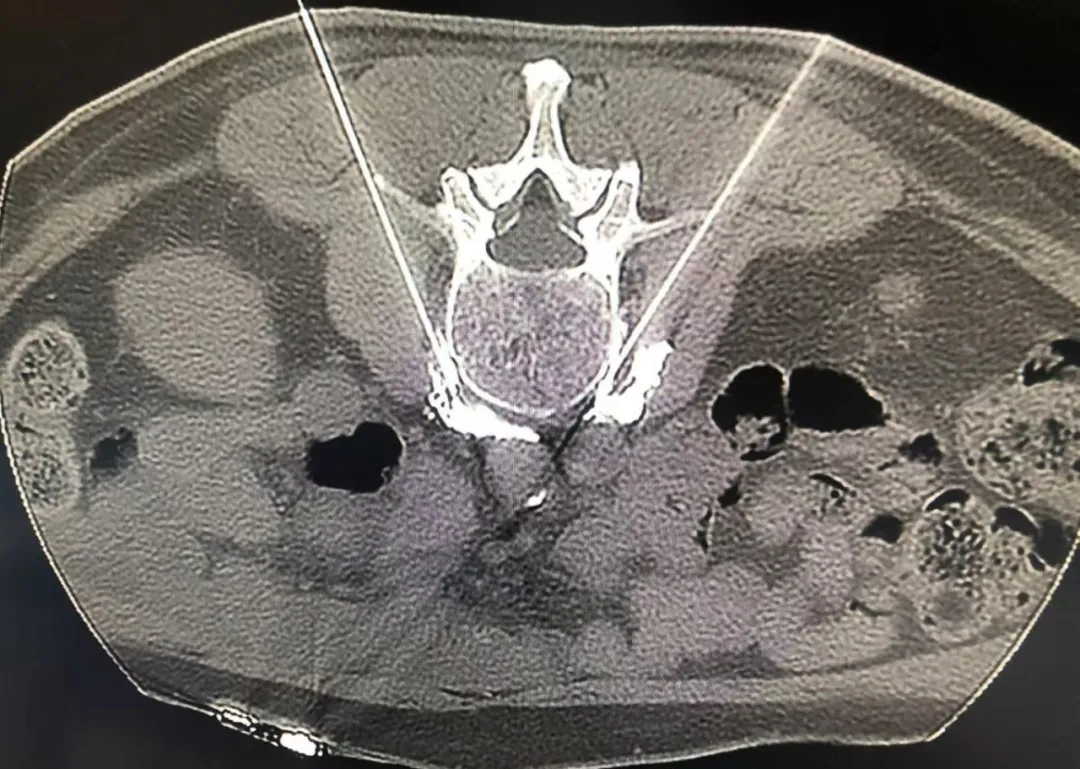

張寧主任結(jié)合其病史和影像學(xué)資料,診斷為糖尿病足周圍神經(jīng)病變。鑒于糖尿病足是糖尿病嚴(yán)重的并發(fā)癥,且隨著時(shí)間的延長疼痛加劇。因此及時(shí)治療糖尿病足疼痛并控制血糖,是緩解患者疼痛和改善糖尿病足患者預(yù)后、提高生活質(zhì)量的關(guān)鍵??紤]到腰交感神經(jīng)化學(xué)毀損術(shù)是應(yīng)用于多種下肢疼痛性疾病治療的先進(jìn)技術(shù),可有效治療糖尿病足疼痛,張寧主任在與楊阿姨及家屬充分溝通后,決定為其實(shí)施超聲CT引導(dǎo)下腰交感神經(jīng)化學(xué)毀損術(shù)。

在完善相關(guān)檢查及術(shù)前準(zhǔn)備后,張寧主任帶領(lǐng)團(tuán)隊(duì)專家在超聲綜合診療中心和影像中心醫(yī)護(hù)人員的在配合下,成功為楊阿姨實(shí)施了手術(shù)。術(shù)后兩個(gè)小時(shí),張寧主任到病房查看楊阿姨的情況,其自述雙下肢的疼痛明顯緩解。楊阿姨激動(dòng)地說:“真是好多了!手也靈活了,腳也熱乎了,也不那么疼了,真是謝謝你們,讓我擺脫了疼痛的折磨,今晚能睡個(gè)好覺了。”家屬感嘆道:“已經(jīng)很久沒看她這么高興了,說話都有精氣神了!”